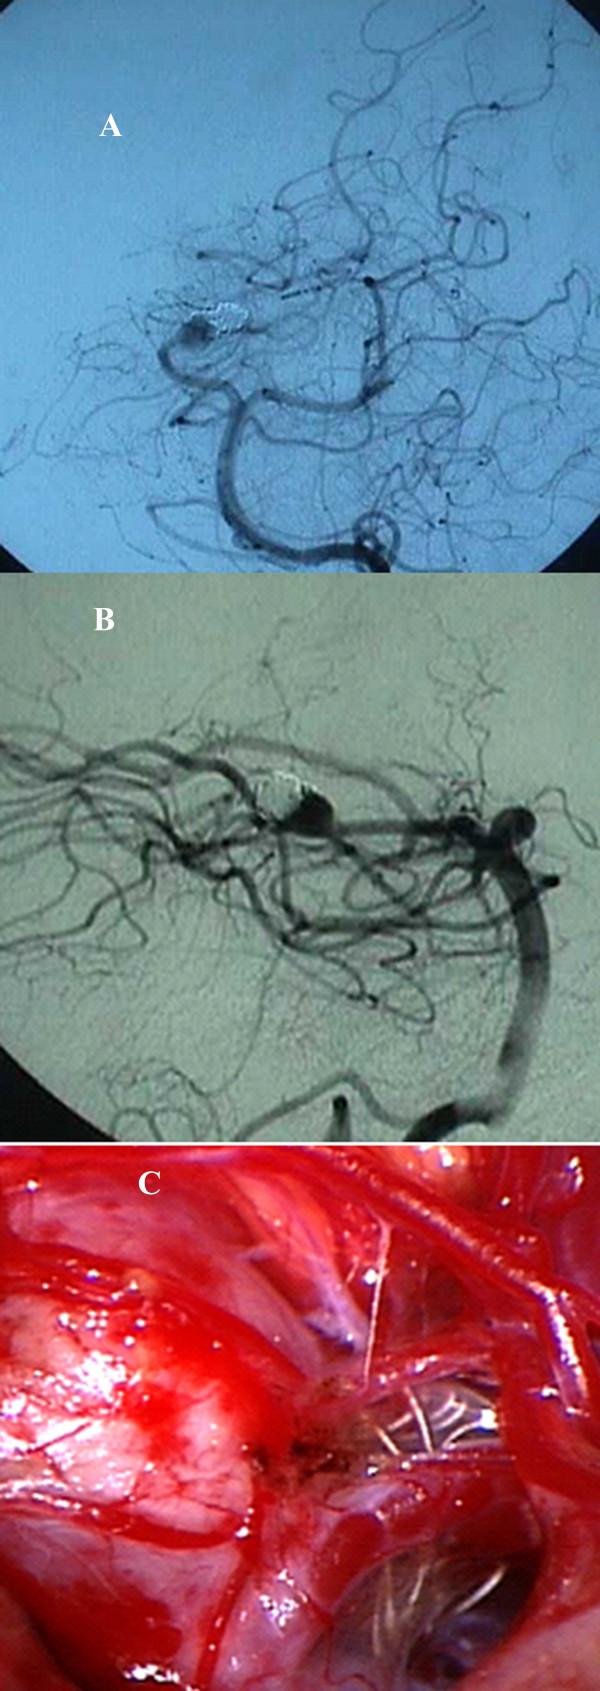

In recent years, technical developments have made endovascular procedures attractive therapeutic options and enabled the endovascular surgeon to redefine the management of cerebral aneurysms. However, as the number of aneurysms undergoing endovascular therapy has grown, so has the number of patients with incompletely treated aneurysms who are presenting for further management. In cases of failure of endovascular treatment caused by either incomplete occlusion or regrowth of the aneurysm, a complementary treatment is often necessary. Surgical treatment of these patients is challenging. We present a case of a ruptured posterior cerebral artery aneurysm treated initially with endovascular coiling that left behind significant residual aneurysmal sac. Regrowth of the aneurysm documented on follow-up was treated surgically. At surgery, the coil was found to have herniated through the aneurysmal sac into the subarachnoid space, and the aneurysm was successfully clipped without removing the coils. We review the regrowth of aneurysms following endovascular therapy and potential problems and challenges of surgically managing these lesions.